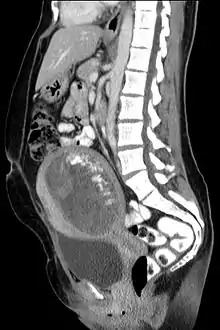

| تصویری از نمای بافتشناختی مول هیداتیفرم. | |